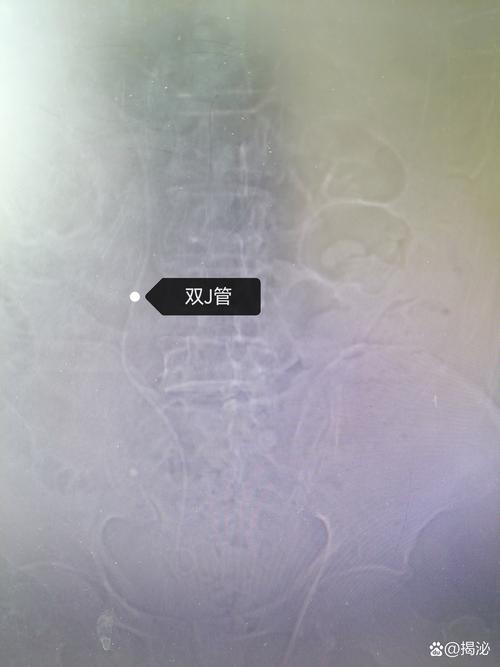

3. 輸尿管支架(Double-J Stent)的重要性與不適

許多輸尿管結石手術後,醫師會在輸尿管內放置一條柔軟的塑膠管,稱為「輸尿管支架」(Double-J Stent)。它的主要目的是:

- 支撐輸尿管:防止術後因水腫導致輸尿管狹窄,確保尿液從腎臟順暢流向膀胱。

- 引流尿液:幫助腎臟功能恢復,避免腎臟積水。

- 擴張輸尿管:為後續可能的碎石或取石步驟做準備(如分段碎石)。

輸尿管支架的存在可能會引起一些不適感,例如:

- 腰部或下腹部疼痛:特別是在排尿時,可能感到腰部或腹股溝處的抽痛,這是因為支架刺激了輸尿管和膀胱。

- 頻尿、尿急:膀胱內有異物感,導致排尿次數增加。

- 血尿:尤其在活動量增加時,支架摩擦可能導致尿液帶血。

這些不適通常在移除支架後會消失。請務必記住醫師告知的支架移除時間,並按時回診。未及時移除支架可能導致感染、結石形成或支架移位等嚴重併發症。

為何輸尿管支架會引起腰痛或血尿?

輸尿管支架(Double-J Stent)是一條從腎臟延伸到膀胱的軟管。它會引起腰痛是因為支架刺激了腎盂和輸尿管,特別是排尿時,膀胱壓力傳導可能導致腎臟部位的牽扯感。血尿則是由於支架在輸尿管內摩擦,尤其在活動時,會造成黏膜輕微出血,導致尿液呈現粉紅色或帶血絲,這通常是正常的現象。